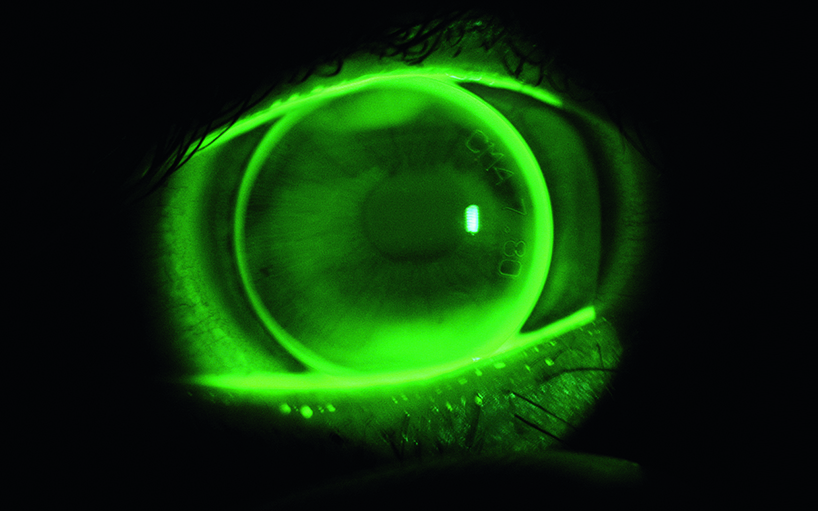

Entwicklung einer speziellen Kontaktlinse, die einen Drucksensor zur Ermittlung des Augendruckes enthält.

Die häufigste Ursache für das Erblinden ist das Glaukom oder der grüne Star. Diese Augenkrankheit ist häufig mit erhöhtem Augeninnendruck verbunden. Der Augeninnendruck variiert, besonders bei Glaukom erkrankten Patienten, im zeitlichen Verlauf stark und für die Diagnostik ist eine kontinuierliche Messung sehr wichtig.

Das Institut für Optometrie hat die Aufgabe übernommen, das Linsendesign, vor allem hinsichtlich physiologische Verträglichkeit und physikalischer Messmöglichkeit, zu definieren.